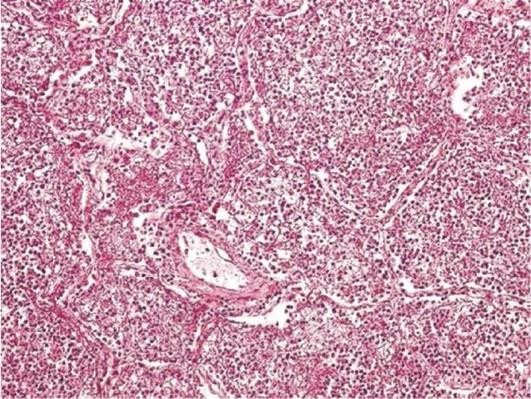

Интерстициальный, или межуточный, миокардит чаще возникает при инфекционном или токсическом воздействии. Выделяют преимущественно экссудативные и преимущественно продуктивные формы интерстициального миокардита (рис. 4.6). При продуктивном миокардите в строме миокарда виден лимфогистиоцитарный и моноцитарный инфильтрат. К межуточным миокардитам относят, например, миокардит Абрамова-Фидлера, имеющий аллергическую природу.